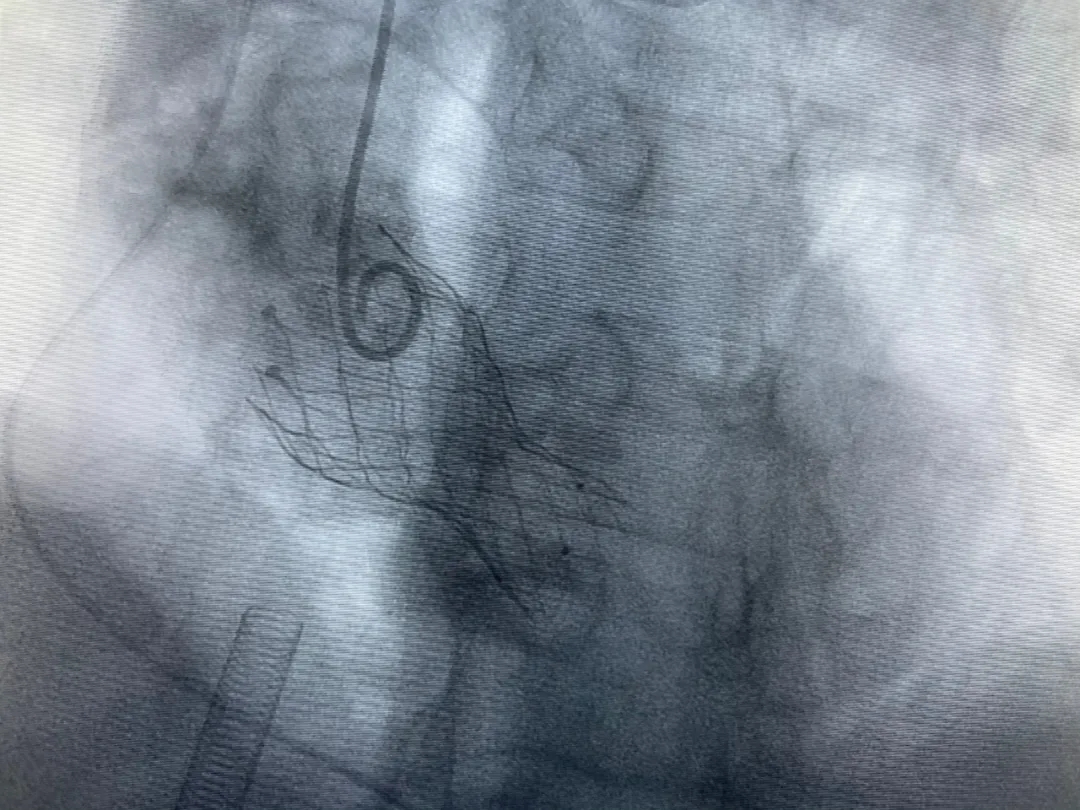

結(jié)合老人病情特點:年齡高、室壁厚、左室腔小、瓣膜鈣化嚴(yán)重,術(shù)中球囊擴張和瓣膜釋放過程有循環(huán)崩潰可能;為降低此種風(fēng)險、最大程度提高手術(shù)成功率,張金洲副院長在術(shù)前組織了由楊金保博士帶領(lǐng)的TAVR團(tuán)隊多次反復(fù)溝通、討論,制定了各種應(yīng)急處理方案。最終經(jīng)過TAVR團(tuán)隊的默契配合,手術(shù)歷時2小時,用20#球囊預(yù)擴張后順利植入23#主動脈瓣生物瓣膜,再次后擴后主動脈根部造影顯示:人工主動脈瓣生物瓣位置良好,瓣葉開閉正常;冠脈顯影良好。經(jīng)食道超聲顯示:主動脈瓣葉活動度良好,主動脈跨瓣壓差約35mmHg,未見瓣周漏及明顯返流。出手術(shù)室前老人便已蘇醒,自訴憋悶癥狀完全消失。